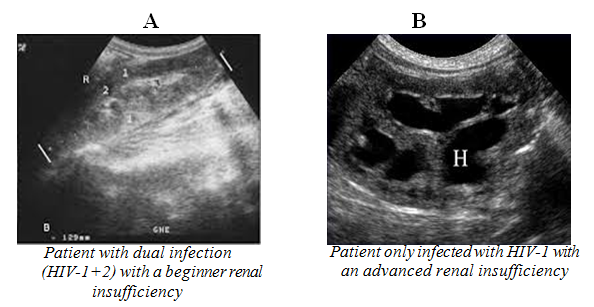

Damage’level of the renal function

All patients with dual infection (HIV-1 and HIV-2) had a nephropathy with a beginner renal insufficiency compared to patients only infected with HIV-1 who presented an advanced renal insufficiency in 96.6% of cases (Table 3) (Figure 2).

Figure 2 Renal ultrasound of a beginner and an advanced renal insufficiency respectively for a patient with dual infection (HIV-1+2)”A” and a patient only infected with HIV-1 “B”.

79(30.8%) patients among the 257 cases of HIV-associated nephropathy had a dual infection (HIV-1 and HIV-2) compared with 178(69.2%) cases for patients only infected with HIV-1. Patients with dual infection (HIV-1 and HIV-2) had a nephropathy with a beginner renal insufficiency compared to those only infected with HIV-1 who presented an advanced renal insufficiency in 96.6% of cases (Table 3). This difference observed among patients with dual infection (HIV-1 and HIV-2) could be explained by the low replicative capacity of HIV-1 in case of coinfection with HIV-2.27 Thus, HIV-1 replication more virulent and faster at the renal level and in the absence of coinfection with HIV-2, leads to cellular changes (apoptosis and phenotypic changes in epithelial cells) and the synthesis of a high rate of inflammatory mediators (including TGFβ and TNFα). These two mechanisms lead to the rapid progression of lesions observed towards the end stage of the renal insufficiency.28,29 In vitro studies have shown that HIV-2 infection generates higher levels of natural beta-chemokine ligands than CCR5 HIV co-receptor mononuclear peripheral blood cells and that this may inhibit HIV-1 infection and its replication at the renal level.20,28,29